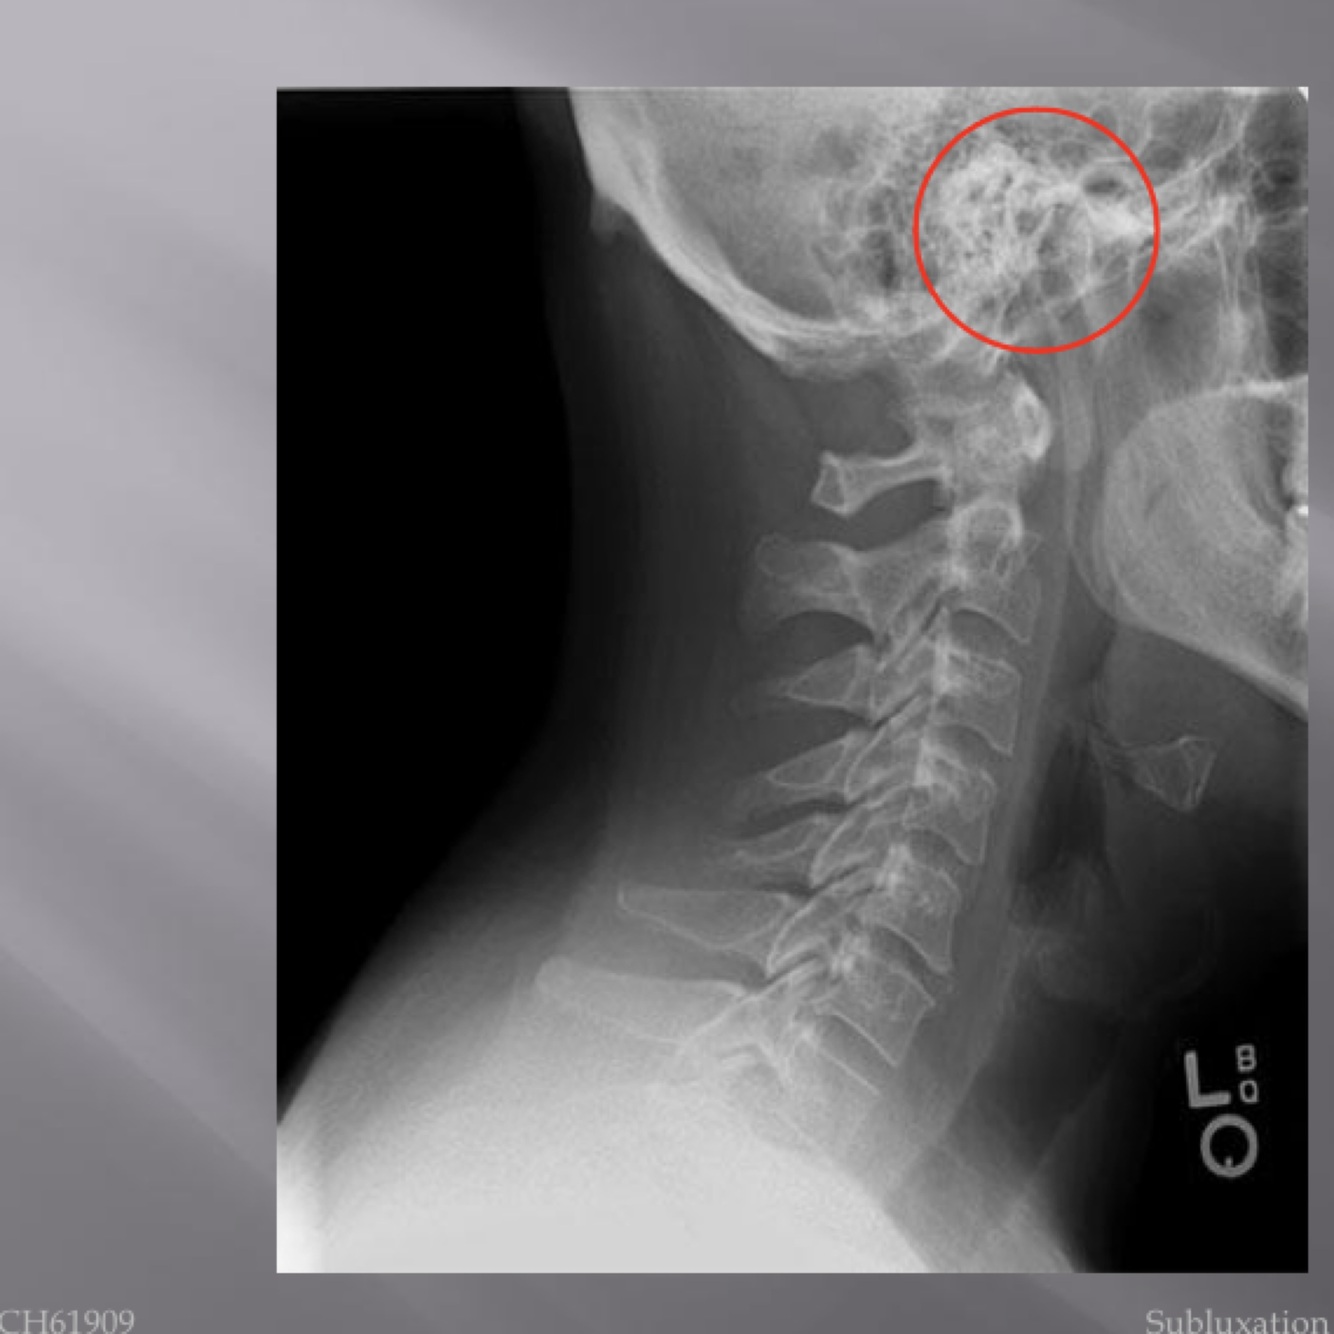

LATERAL CERVICAL LANDMARKS lateral cervical view

external acoustic meatus

mastoid process (air cells)

posterior tubercle of c1

angle of mandible

EOP

spinous process C2-C7

sella turcica

dens

posterior arch of C1

lamina c2-c7

uncovertebral joints (joints of luschka)

vertebral body c2-c7

lateral masses c1

rami of mandible

articular processes

body of mandible

transverse process of c2-c7

anterior tubercle c1

zygapophyseal joints

frontal sinus

petrous portion

occipital condyle

superior endplate tips

inferior endplate tips

Lateral cervical view

disc spaces

26

atlanto-dental interspace

27

hyoid bone